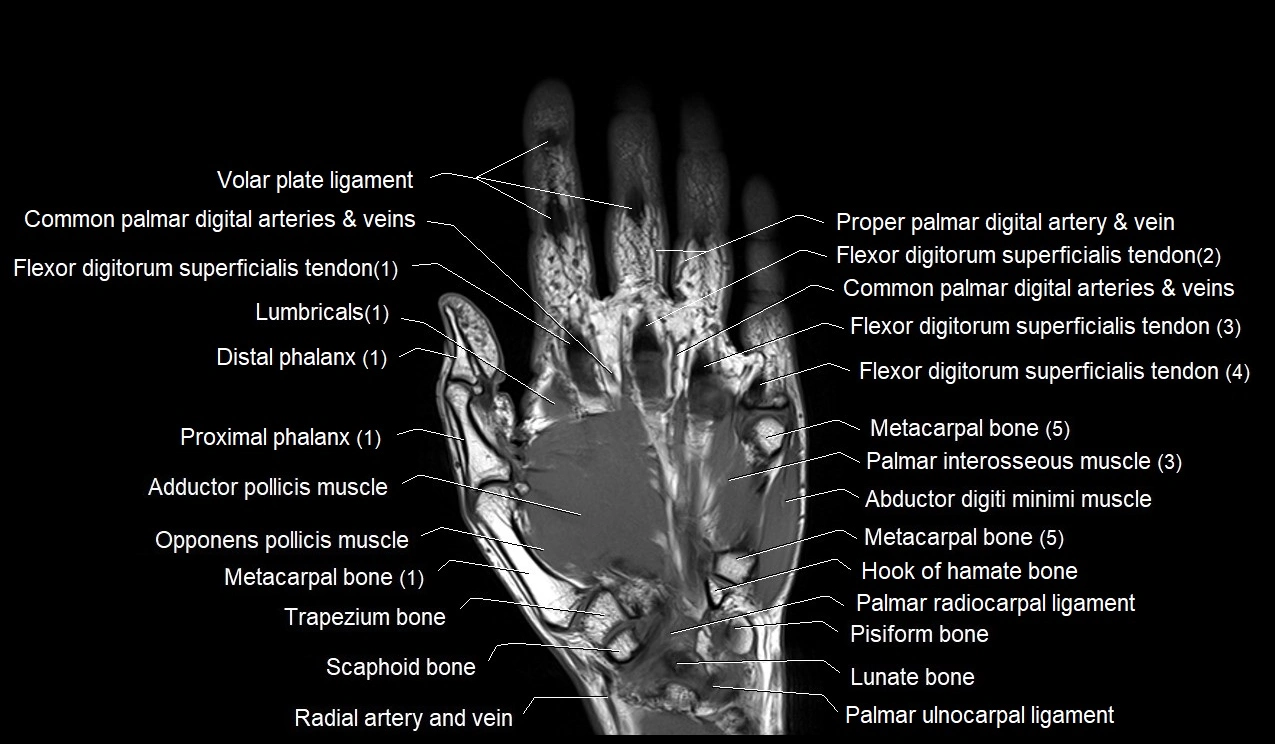

- Abductor digiti minimi muscle (hand)

- Adductor pollicis muscle

- First flexor digitorum superficialis tendon

- First metacarpal bone (metacarpal I)

- Flexor digitorum superficialis tendons

- Flexor retinaculum of wrist

- Hamate

- Hook of hamate bone

- Lunate

- Opponens pollicis muscle

- Palmar interosseous muscles of hand

- Pisiform

- Scaphoid

- Trapezium